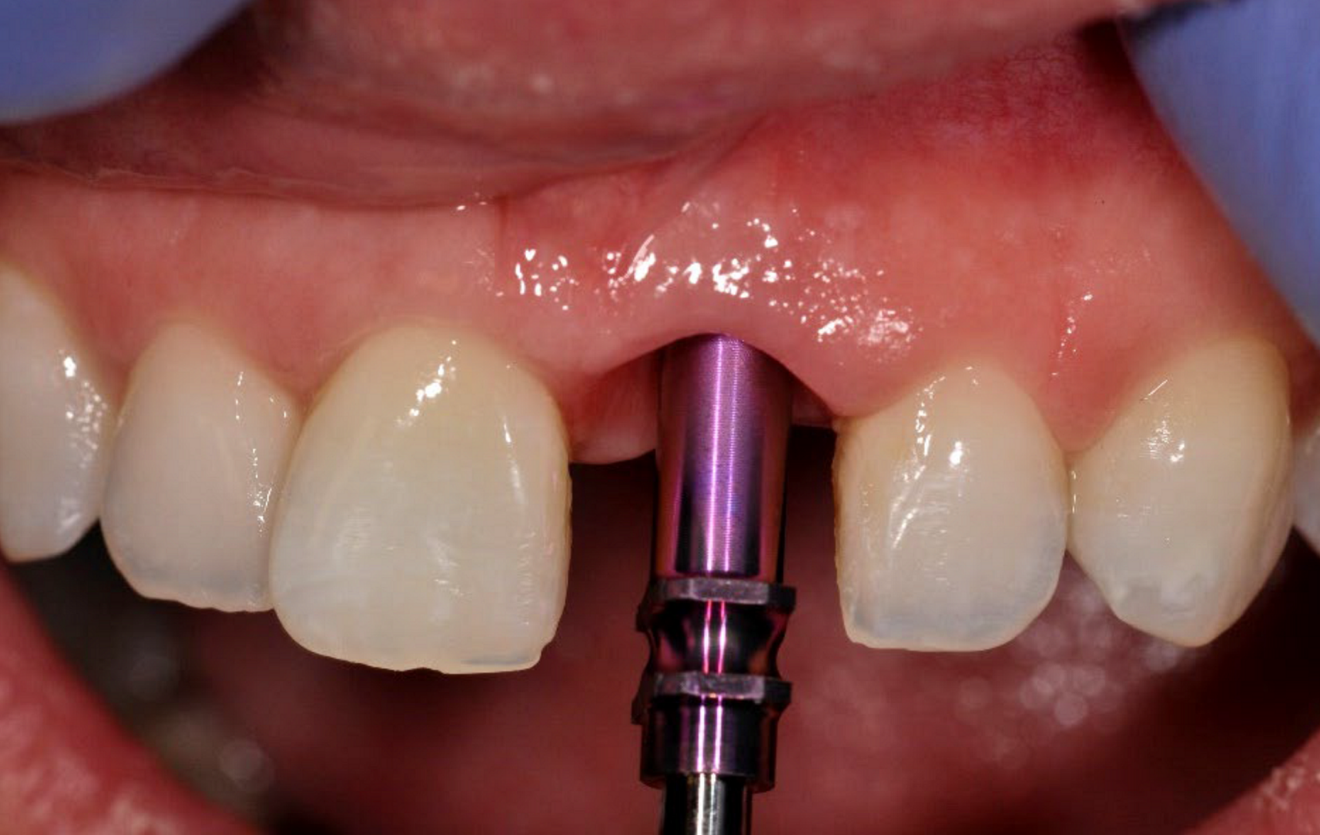

Healing abutment (e) ...

... and the resulting contoured tissue at 12 weeks post-op (f).